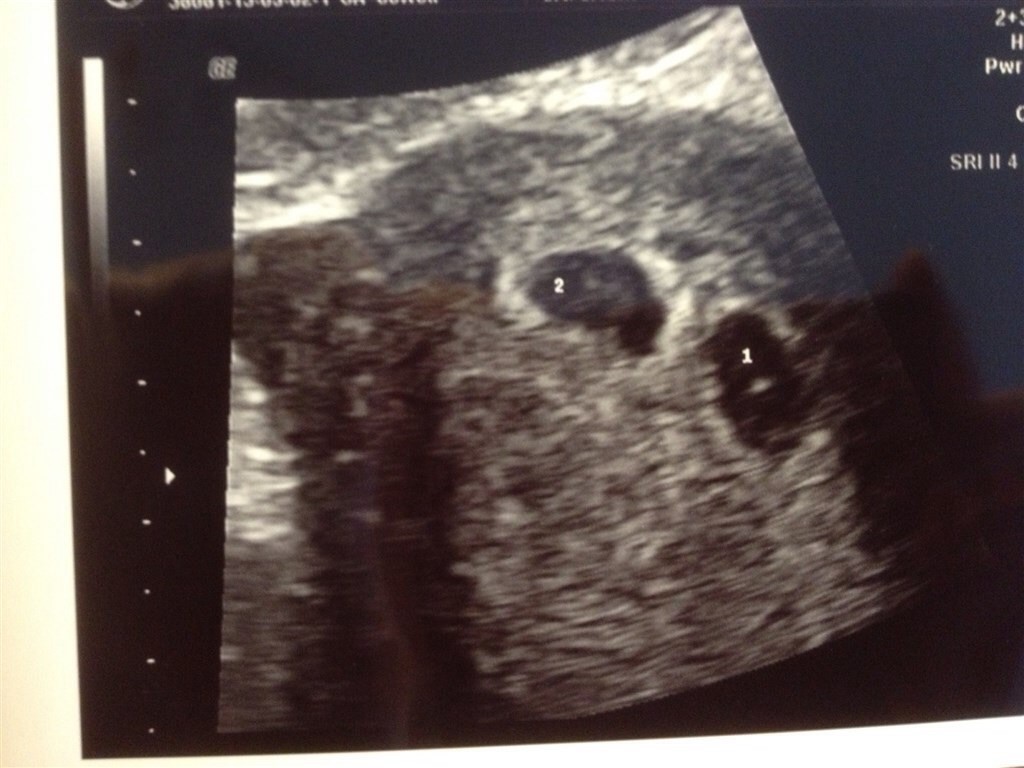

Det her er billeder fra vores tryghedscanning med bøllerne. Jeg er 6+1 og der hvor hjerteblink..

Vedhæftede fotos (klik for at se i fuld størrelse)